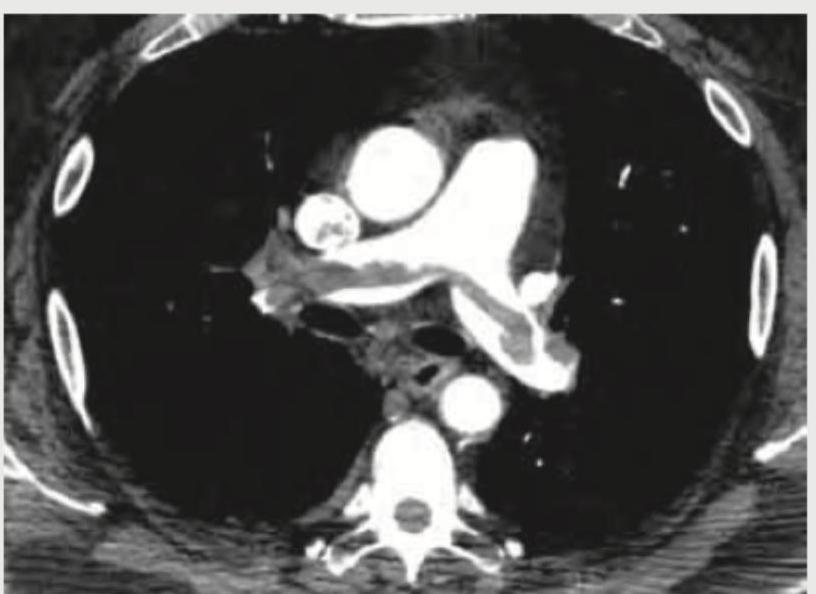

Comment on the diagnosis of the CT chest image shown below.

The CT thorax image shows:

Which of the following is shown in the image below?

A 35-year-old male with history of 4 weeks of immobilization for fracture of femur develops sudden onset breathlessness and blood in sputum. CT angiography shows? (Recent NEET Pattem 2018-19)